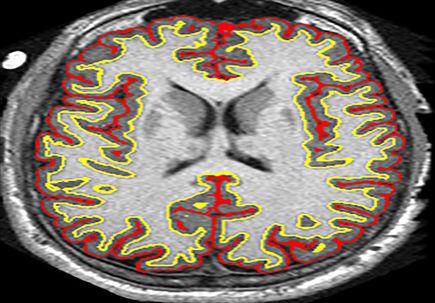

The major finding of the pilot study involved measuring the degree to which lipoic acid arrested the rate of whole brain atrophy, as measured through magnetic resonance imaging.

The study revealed a 68 percent improvement over the placebo in slowing the rate of whole brain atrophy in patients with secondary progressive MS. For the sake of comparison, a clinical trial involving the recent FDA-approved pharmaceutical Ocrevus showed an 18 percent improvement over a placebo in slowing the rate of whole brain atrophy for patients with primary progressive forms of the disease.